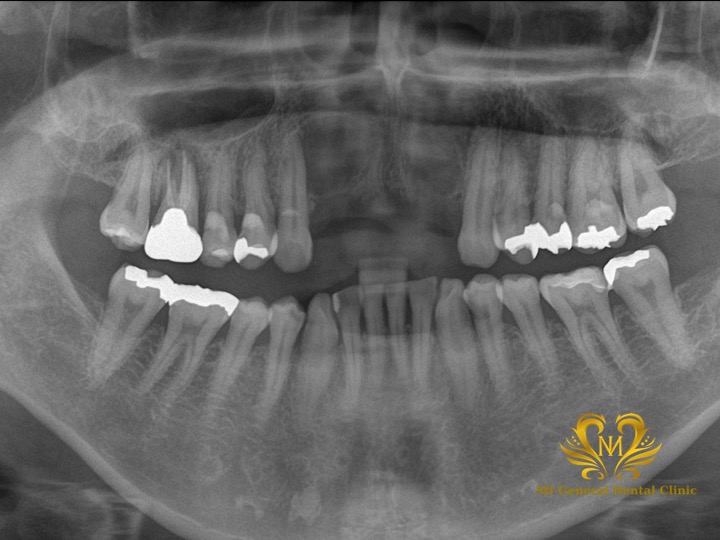

治療前

前歯4本がなく、CTでも本当に骨が残っていませんでした。

治療後

インプラント体と骨とセラミックスの被せ物が綺麗に合っています。

| 治療内容 | 骨造成後にインプラント体の埋入を行い、インプラント体に負担をかける仮歯にかえて、調整を行い、セラミックスの被せ物の型取りを行い、完成です。 ※最初のうちは周りに歯に仮歯を接着して支えてもらい、見た目の問題は回避しました。 |